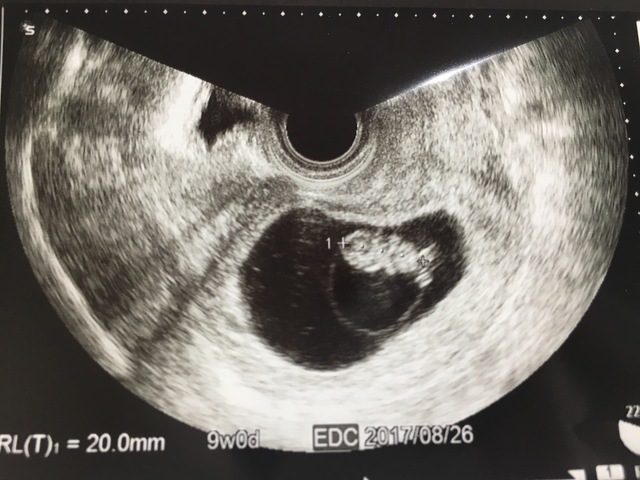

9週0日(9w0d・男の子・双子)|なおねこ さん(29歳)

エコー写真撮影時のエピソード:

妊娠9週目で双子と明らかに分かった写真です。

双子が欲しいと思っていたのでとてもびっくりしたし、初めての妊娠でびっくりと不安が入り混じった心境でした。また、病院も紹介された大学病院での初診だったのでとても緊張しました。